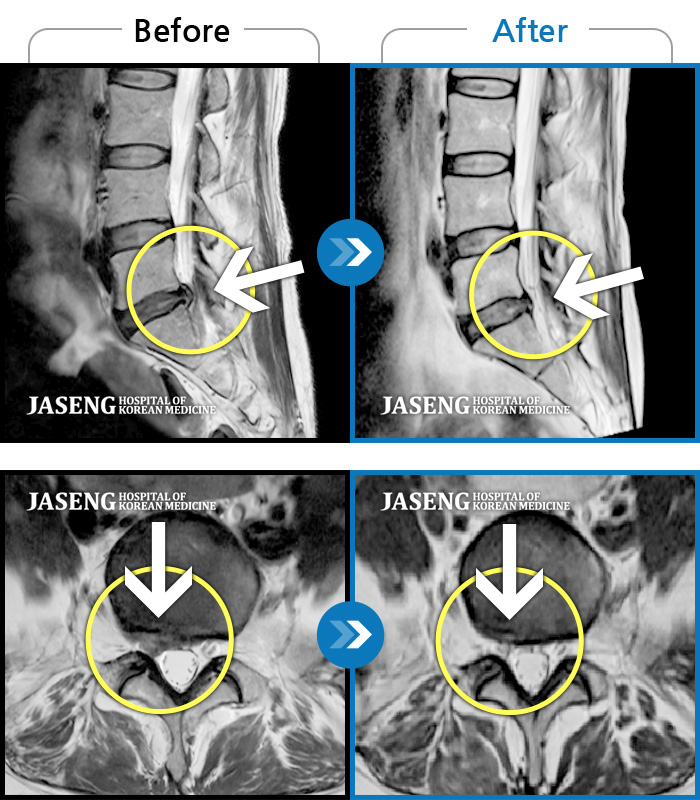

컴퓨터 모니터로 많이 튀어나온 디스크도 쑥 들어간 mri사진 사례들을 여러개 보여주시며 이보다 더 많은 사례가 있다고 제게 희망을 주셨습니다